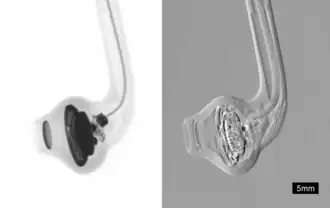

Der entscheidende Vorteil der phasensensitiven Methoden liegt darin, dass sie röntgentransparente Objekte wie Weichteilgewebe sensitiver abbilden können.[1] Zusätzlich können streuende Objekte wie das Lungengewebe kontrastreich abgebildet werden. Dabei wird ausgenutzt, dass Röntgen-Kleinwinkelstreuung des durchleuchteten Objekts eine Schwächung des erzeugten Interferenzmusters bewirkt.[2] Aufgrund von Ähnlichkeiten zur Dunkelfeldmikroskopie wird das durch Streuung zustande kommende Bild auch als Röntgendunkelfeld bezeichnet. Herkömmliche Röntgenbildgebung wie z. B. die Radiographie oder Computertomographie basieren bis heute hingegen nur auf der Abschwächung der Strahlintensität (Lambert-Beer Gesetz) durch das abzubildende Objekt und erzeugen so nur einen niedrigen Kontrast zwischen Objekten ähnlicher materieller Zusammensetzung.

Die verschiedenen technischen Realisierungen zur Erzeugung von Röntgen-Phasenkontrast-Bildern werden insbesondere für Anwendungen in der Medizin, Biologie und Materialwissenschaften entwickelt. Potentielle klinische Anwendungen werden derzeit in vorklinischen Studien erschlossen.[3]